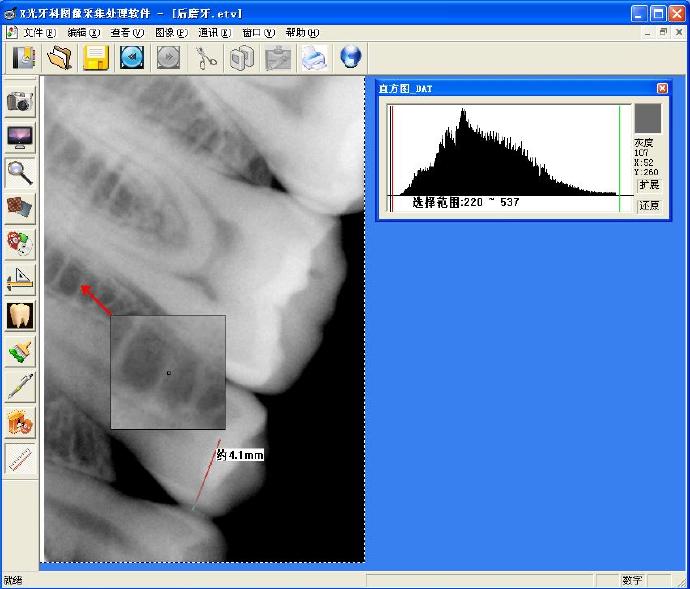

2009年,设计完成了基于英国E2V牙科口内X射线CCD的成像电路设计。设计采用了FPGA(现场可编程门阵列)及高精度ADC,通过高速USB2.0进行高速数据传输。实验结果表明:牙科口内数字成像系统分辨率15lp/mm。该X射线数字成像系统具有体积小、结构简单、分辨率高的特点,能够满足牙齿及指关节等部位实时诊断和工业X射线检测的要求。

本文介绍了一种基于英国E2V牙科口内X射线CCD的成像电路设计,该设计采用FPGA及高精度ADC,并通过USB2.0进行高速数据传输。系统具有体积小、结构简单、分辨率高等特点,适用于牙齿及指关节等部位的实时诊断。